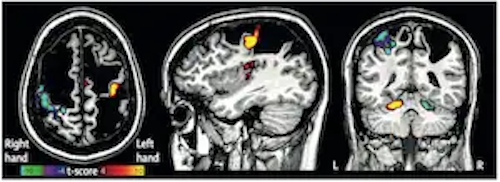

Nico Dosenbach, MD, PhD, scanned his 13-year-old patient in 2012 and found he had suffered a massive perinatal stroke and lost large parts of his brain. Defying logic, Daniel's now an athletic college graduate. Read more in @washingtonpost: washingtonpost.com/health/perinat… #MIRpatientcare